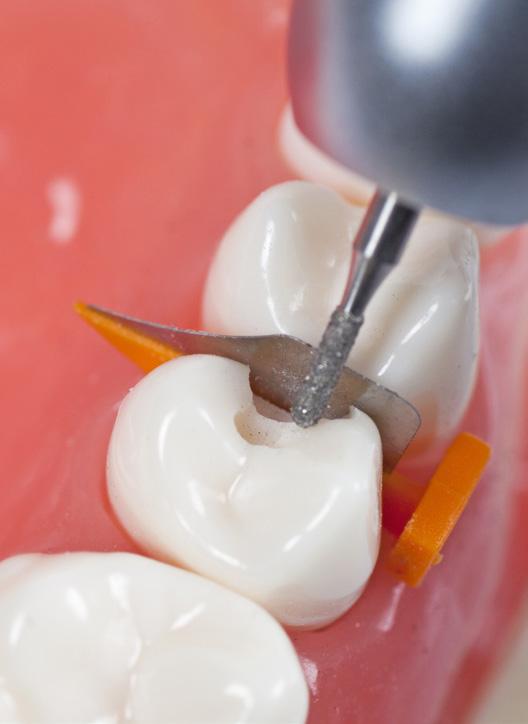

Root n’ screw Brush™

Roterende børste perio/implantat

-25% på Root n’ screw Brush™

Gjelder til 30.06.2024

Vi sender deg gjerne en prøve med din ordre!

CMS Root n’ screw brush er roterende, engangs depurasjonsbørster utviklet i samarbeide med prof. dr. Claudio Mongardini fra Italia. For rene overflater og implantater. Brukes ved 200 til 600 omdreininger på vinkelstykket. Børstefibrene er laget av nylon. Finnes i to størrelser, gult skaft (D2) med børstediameter på 2mm, og oransje skaft (D3) børstediameter på 3mm. Lengden på begge er 37mm. Børstene kan brukes i større, åpne lommer og i furkaturer. Børstene kan autoklaveres før bruk om ønskelig. Leveres i 6-pk. Før 288,-